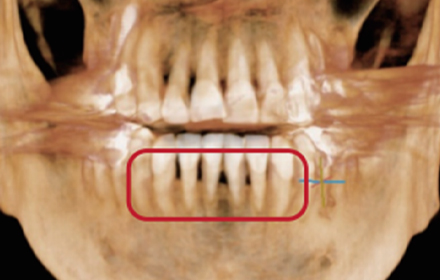

엑스레이로 확인 가능한

치아 뿌리 쪽의 염증

엑스레이 촬영

치아 뿌리 부근의 염증 주머니

다소 시간이 걸리더라도 발치 후 엑스레이 촬영 등을 통해 남아있는 염증을 파악 후 완벽하게 제거합니다.

발치 후 완벽하게 제거되지 못한 염증은 치근낭을 유발하여 발치 치아 주변 건강한 치아와 잇몸까지 염증을 유발하기 때문에 꼭 필요한 과정입니다.